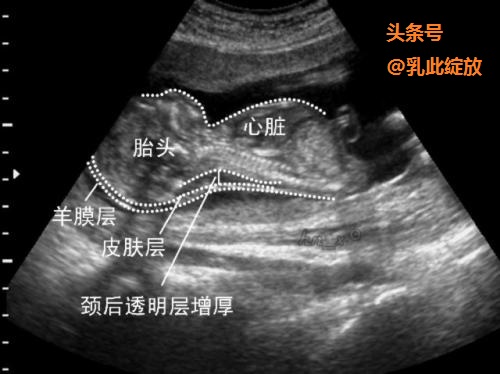

国内大部分的产科中心,选择 2.5mm 作为临界值, 即 NT≥2.5 mm 时视为异常增厚。小于2.5mm的都称为过关了。

NT异常增厚

NT不过关,并不意味着胎儿一定有问题。但目前很多研究显示:NT异常增厚与胎儿染色体异常、胎儿畸形、胎儿宫内生长受限及多种遗传综合征相关。如: 21-三体,胎儿先天性心脏病等等。如NT不过关,则需进一步的产前诊断:无创产前DNA检测、无创胎儿染色体非整倍体检测、羊水穿刺等等。

胎儿 NT 增厚与胎儿发育异常有着密切的关系。由于 NT 检查具有直观性及非介入性等优势,是评价孕早期胎儿不良是临床结局的一项重要依据。同时通过 NT 筛查, 可使介入性检查更具有针对性, 明显降低孕早期缺陷儿的出生率。建议每个准妈妈都进行NT检查。